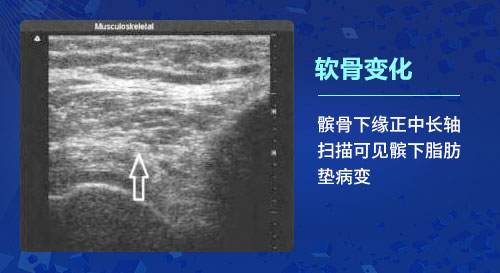

一、软骨变化:骨关节炎的基本病理改变是软骨变性,出现软骨细胞纤维化、骨质增生及滑膜炎等改变。肌骨超声检查能够发现骨关节炎患者初始的软骨改变,在软骨的厚度基本上没有发生实质性变化的时候就可以发现软骨透声模糊、边缘毛糙等细微的变化;利用高分辨率能力,检查软骨完整性(毛糙、变钝、分布不均)及厚度、软骨透声的清晰程度以及软骨表面的轮廓光滑度的变化,甚至出现局限性变薄或消失,以此很好的反映骨关节炎各个阶段的病理变化。